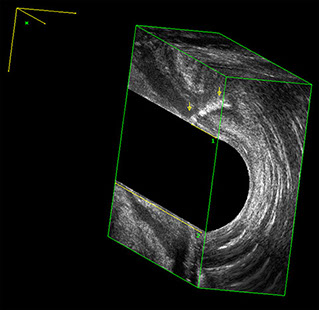

L’ecografia transanale è un esame diagnostico per immagini che consiste nell’introduzione di un trasduttore ad ultrasuoni. Le immagini qualitativamente migliori del canale anale sono ottenute usando un trasduttore rotante, montato in un manipolo rigido, che fornisce un’immagine a 360°. Con le apparecchiature più moderne è anche possibile ottenere immagini tridimensionali.

Proctal dispone di apparecchiatura per ecografia endoanale 3D con sonda rotante.

Sezione Longitudinale 3D con Tramite Fistoloso Intersfinterico Basso Anteriore Semplice